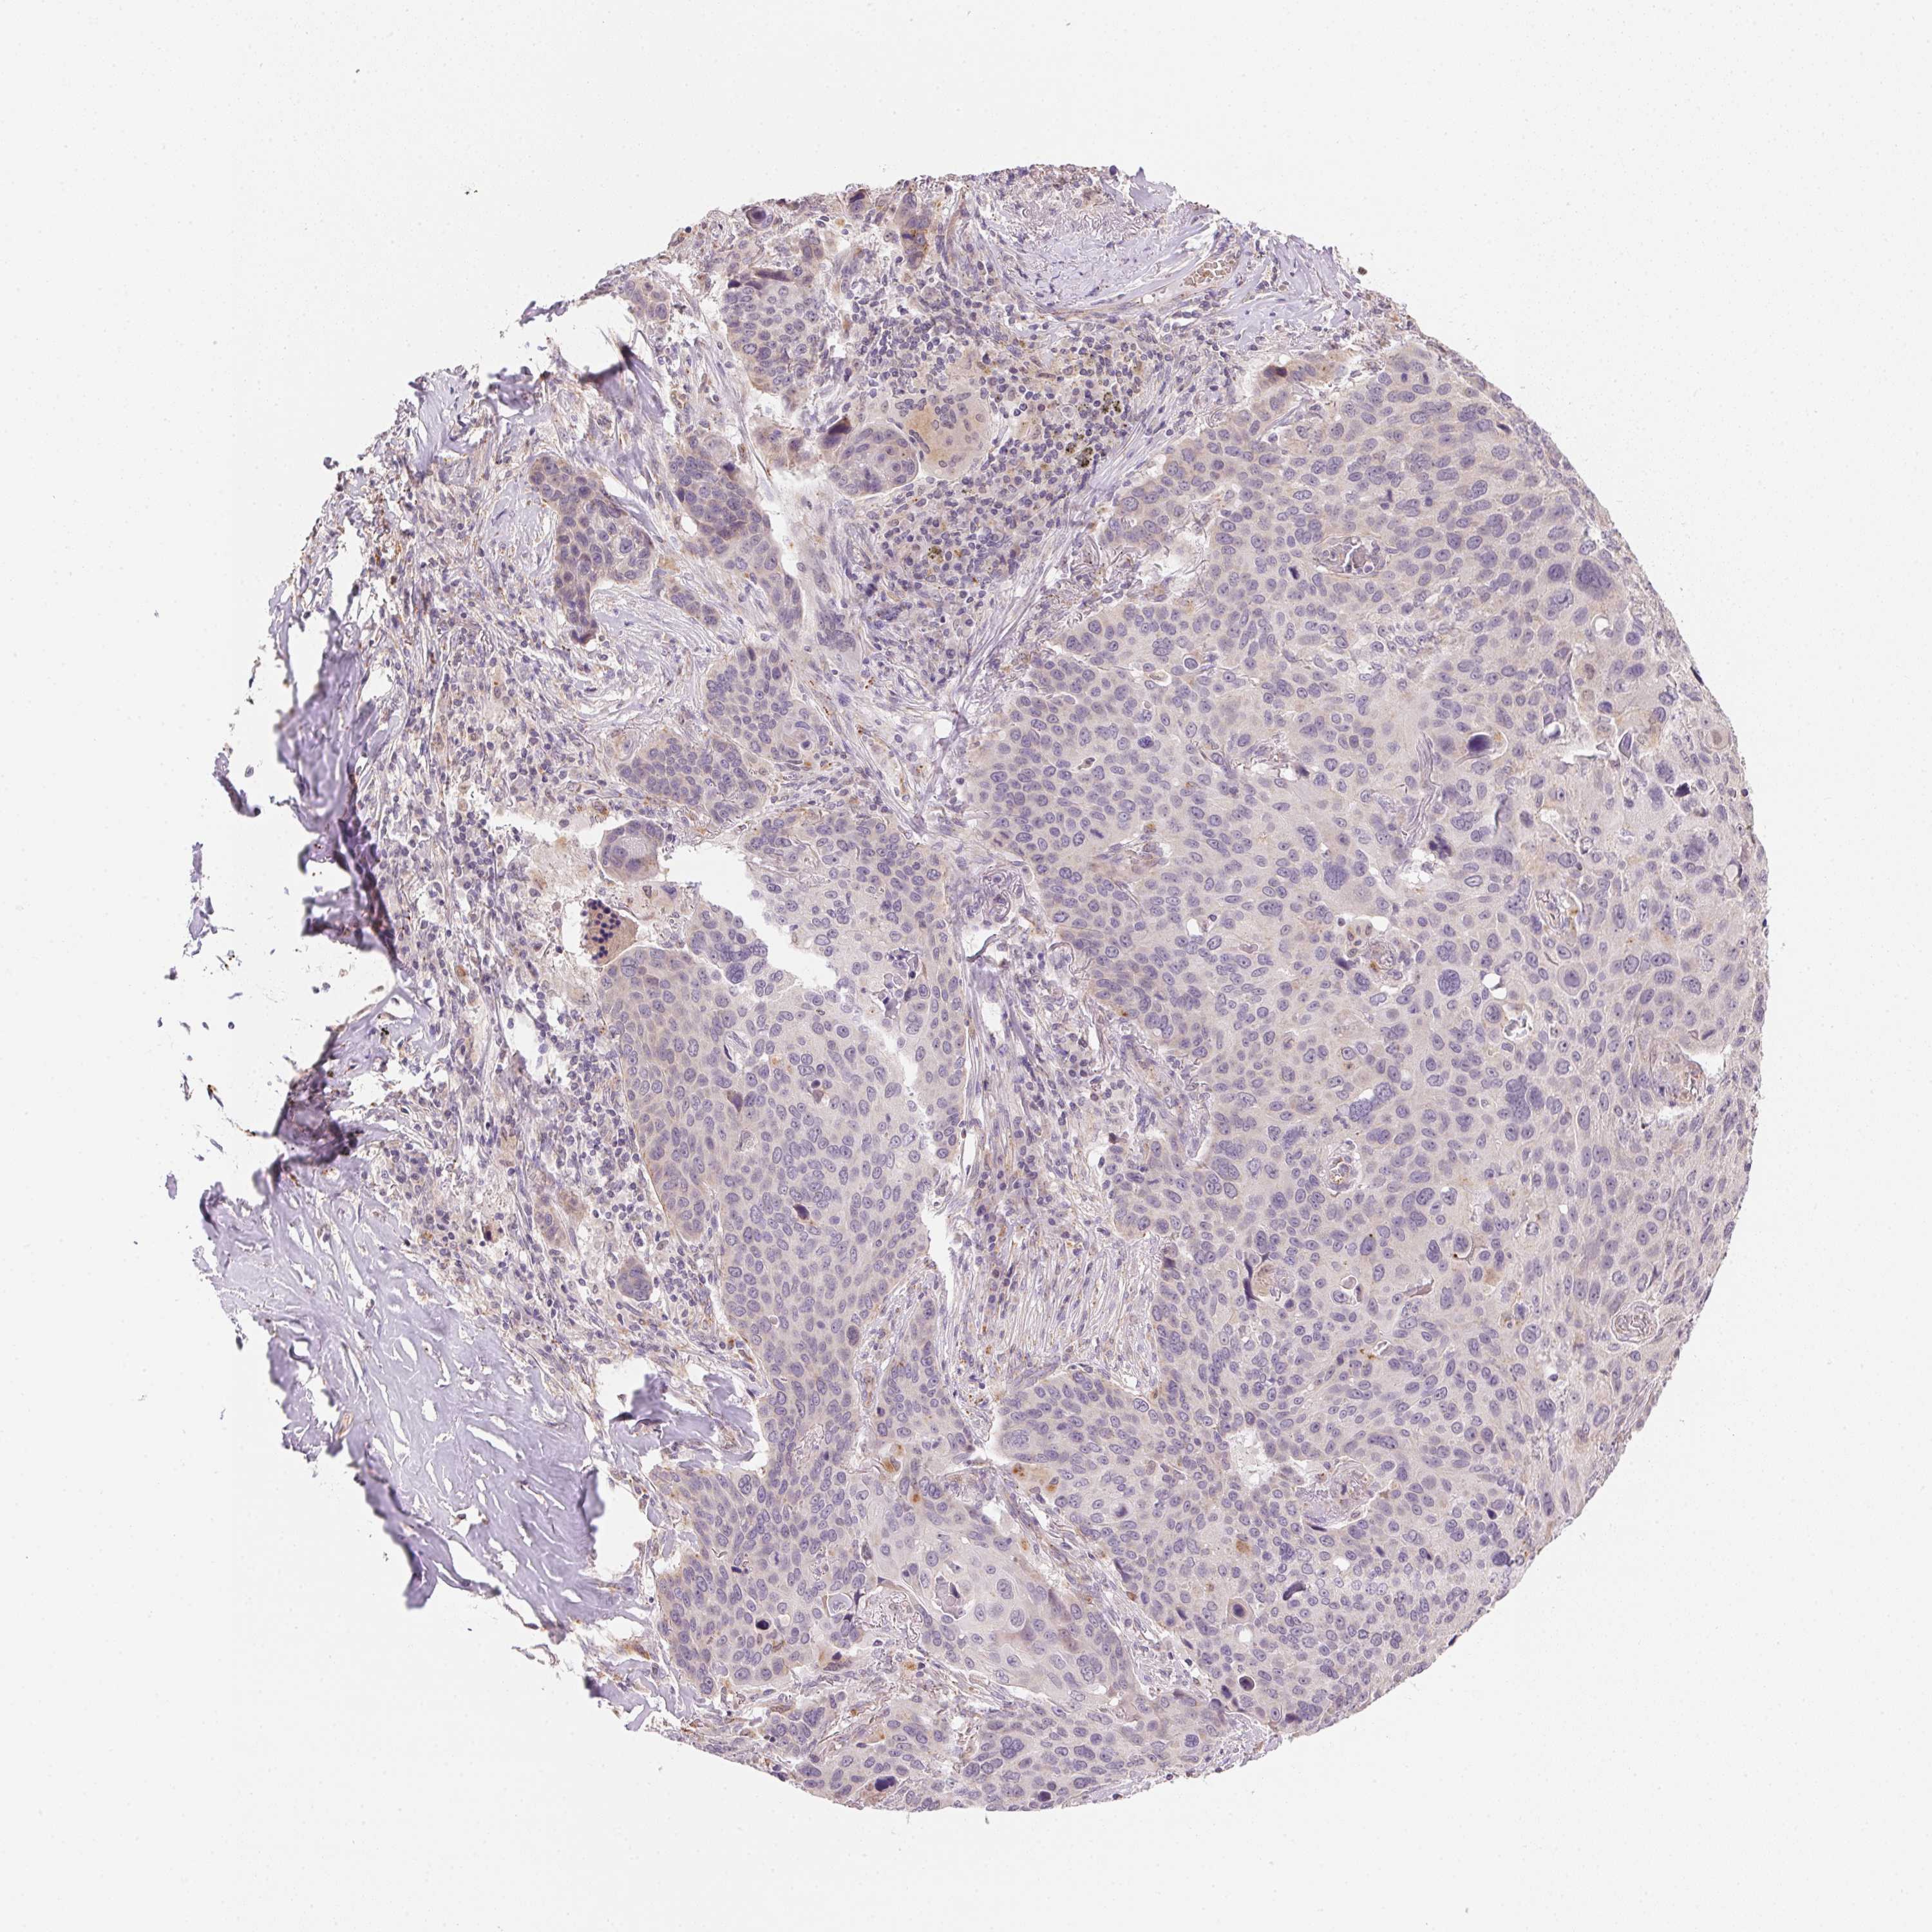

CANCER LUNG CANCER Show tissue menu